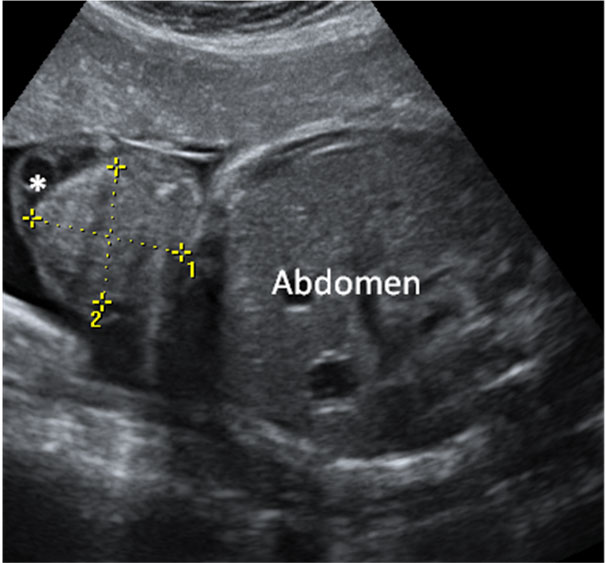

Corazón fetal en el que se aprecia una mancha brillante o foco ecogénito

La imagen de la flecha indica el foco ecogénito en el ventrículo izquierdo.